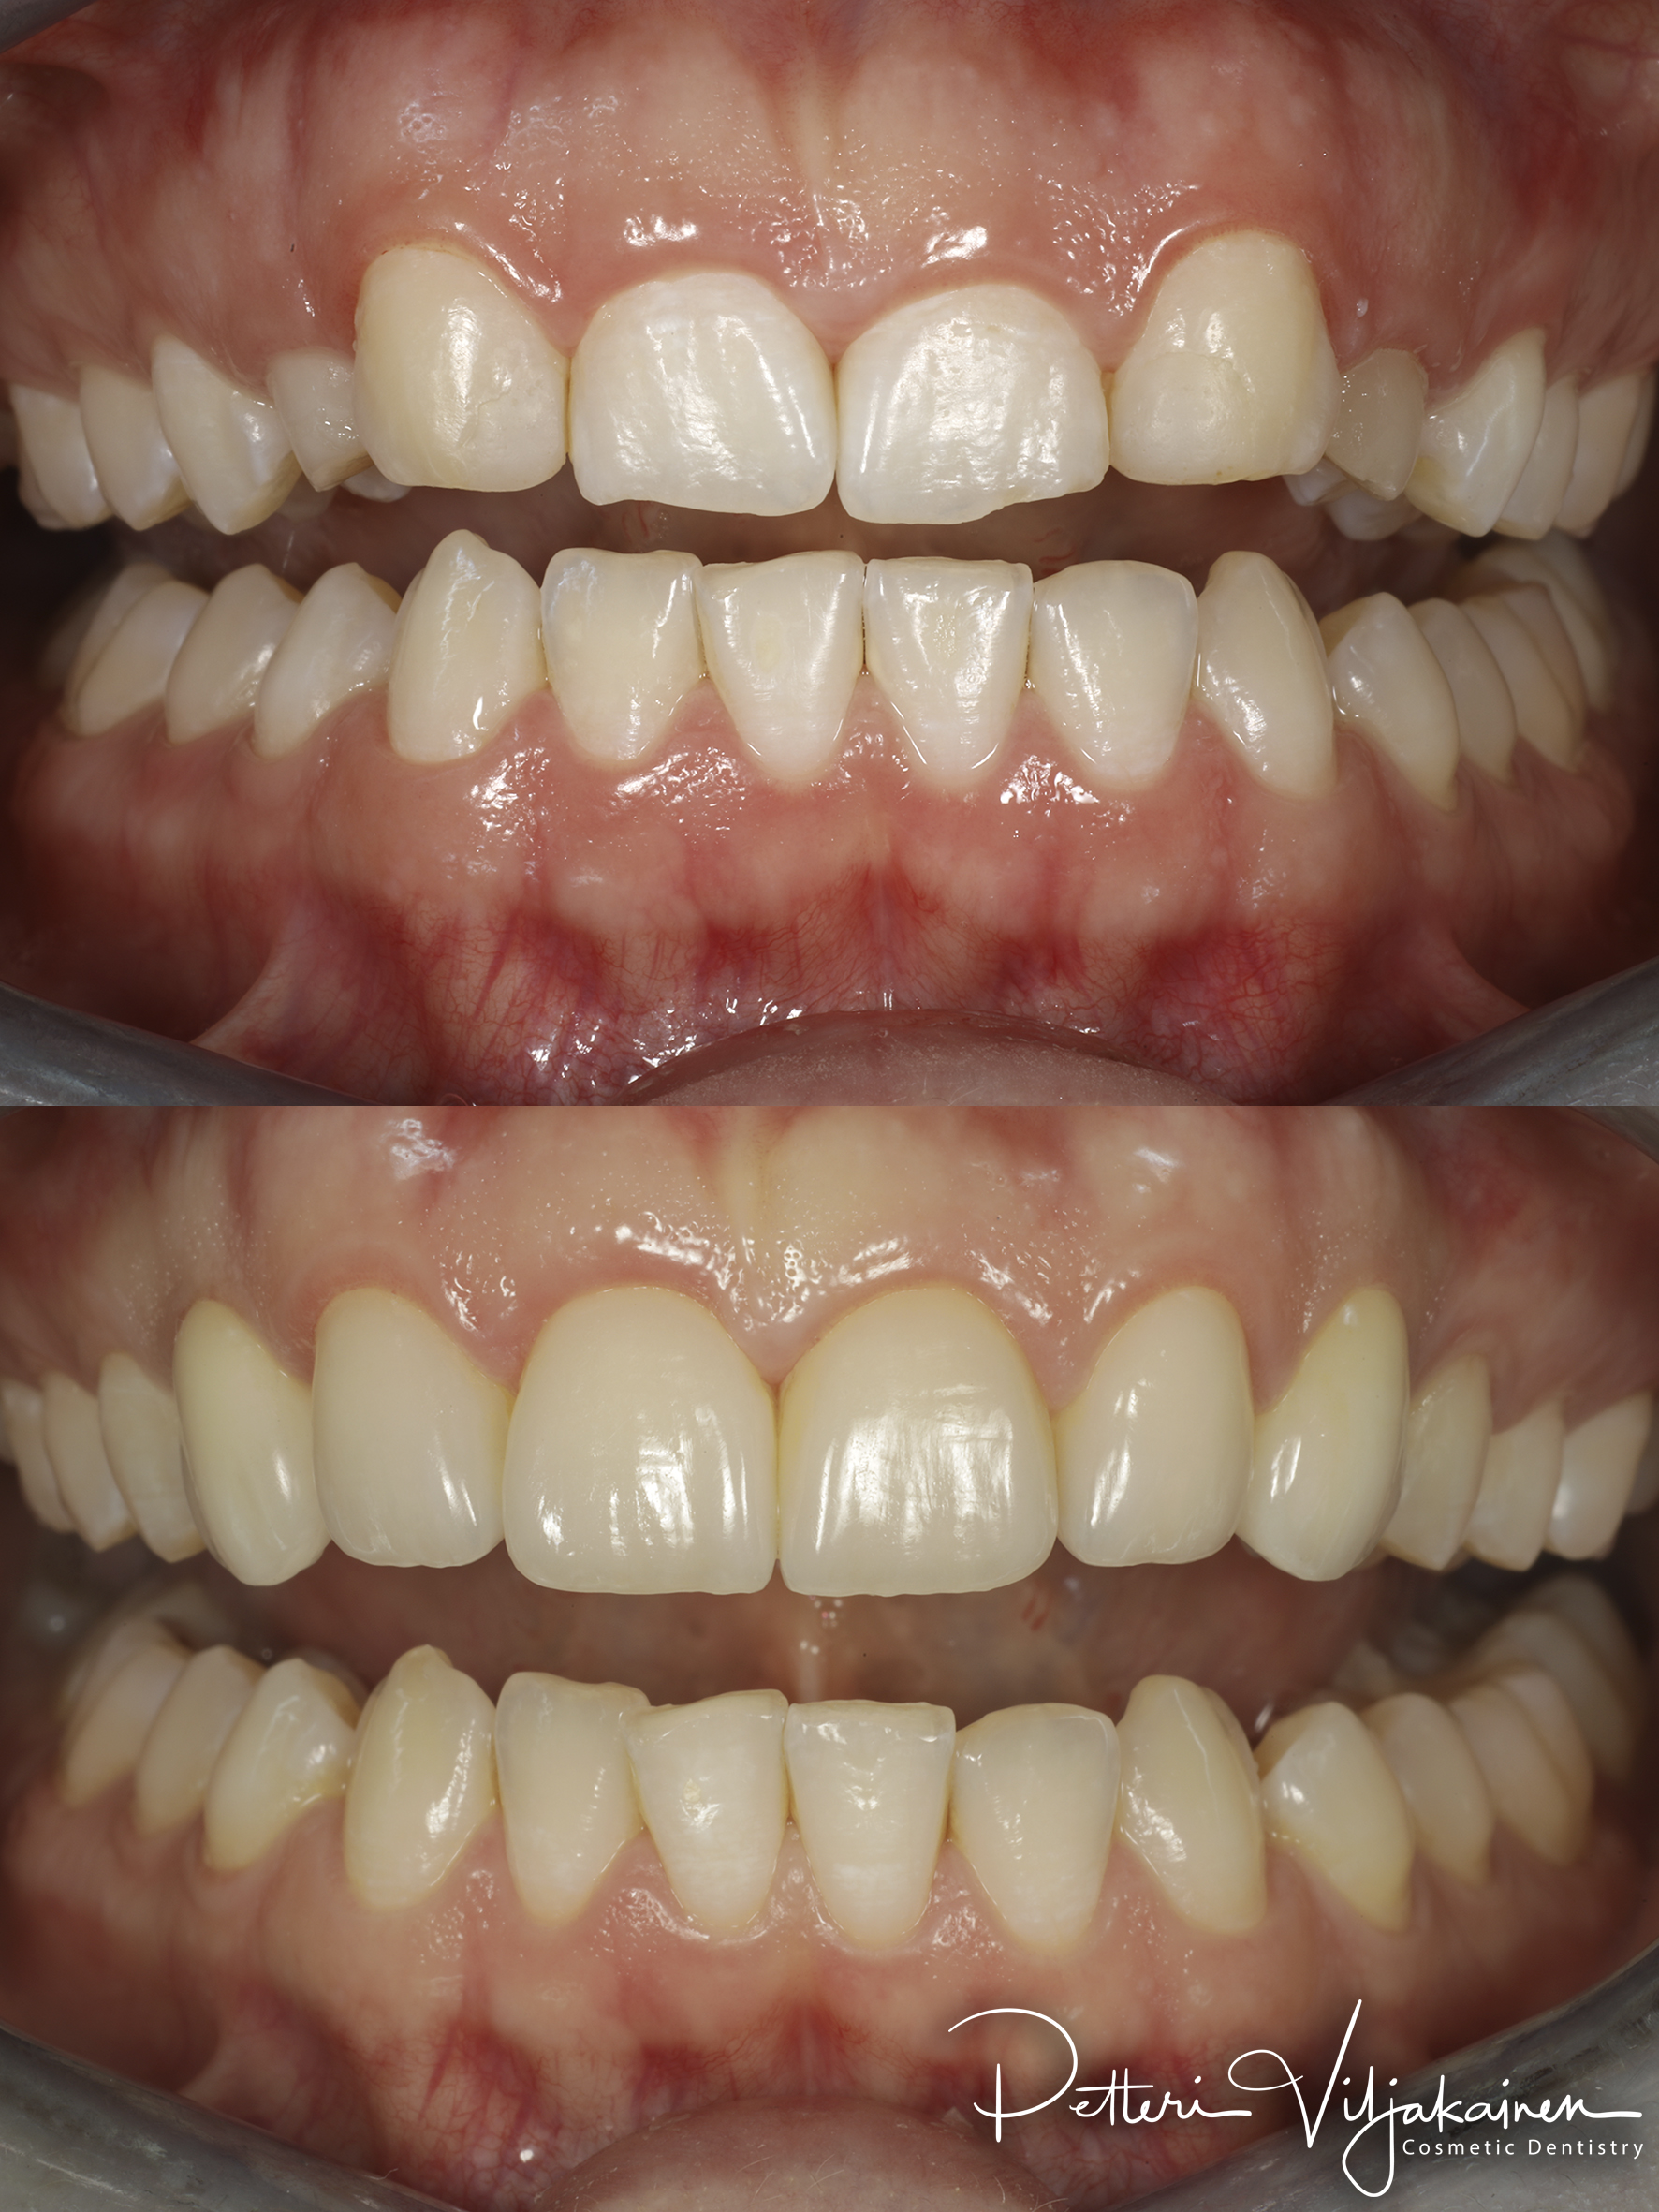

Alla suorittamiani hoitoja ja esimerkkejä siitä minkälaisia purentavirheitä voi korjata.

20kk hoito (Comprehensive).